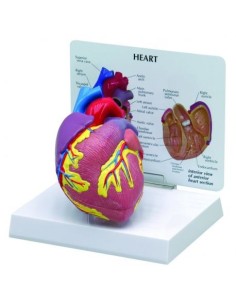

Dal cranio in 22 parti con incastri magnetici ai modelli di colonna vertebrale, da quelli di articolazioni a quelli di cuore, ogni pezzo della nostra collezione è progettato per un’immersione totale nello studio dell’anatomia umana. I nostri modelli, realizzati tramite scansioni di ossa vere, garantiscono un’esperienza tattile autentica e una fedeltà di peso quasi identica agli originali.

Essenziali per studenti e professionisti, i nostri modelli anatomici sono strumenti didattici che permettono di osservare le strutture anatomiche con precisione, eliminando la necessità di dissezioni o studi invasivi. Sono inoltre utili per spiegare ai pazienti le patologie, rendendo la comunicazione più efficace e risparmiando tempo prezioso.